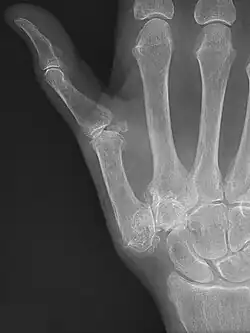

Diagnosis

TMC OA is diagnosed based on symptoms and signs.[8] Radiographs can confirm the diagnosis and the severity of TMC OA. Other diagnoses in this region include scaphotrapezial trapezoid arthritis and first dorsal compartment tendinopathy (De Quervain syndrome) although these are usually easy to distinguish.

TMC OA severity was classified by Eaton and Littler which can be simplified as follows:[21][22]

Stage 1:

- slight widening of the joint space

- < 1/3 subluxation of the joint (in any projection)

Stage 2:

- Osteophytes, < 2 mm in diameter, are present. (usually adjacent to the volar or dorsal facets of the trapezium)

Stage 3:

- Osteophytes, > 2 mm in diameter, are present (usually adjacent to the volar and dorsal facets of the trapezium)

- Slight joint space narrowing

Stage 4:

- Narrow joint space

- Concomitant scaphotrapezial arthritis

A simpler classification is no arthritis, some arthritis, and severe arthritis.[23] This simpler classification system omits the potentially contradictory details of the Eaton/Littler classification and keeps scaphotrapezial arthrosis separate.